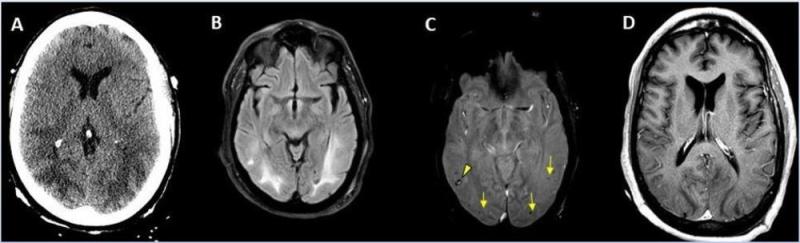

CT showing hemorrhage in a 68-year-old male patient with COVID-19 infection. Image courtesy of RSNA

-

A 62-year-old male with a past medical history of hypertension presenting with seizures. Image courtesy of RSNA

A 56-year-old male patient with diabetes and hypertension who presented with complaints of confusion. Courtesy of RSNA

Hemorrhage seen in 56-year-old female with COVID-19 infection and no other significant past medical history. Courtesy of RSNA

A 65-year-old male smoker, presented with acute hypoxic respiratory failure secondary to COVID-19 pneumonia, requiring intubation. Courtesy of RSNA